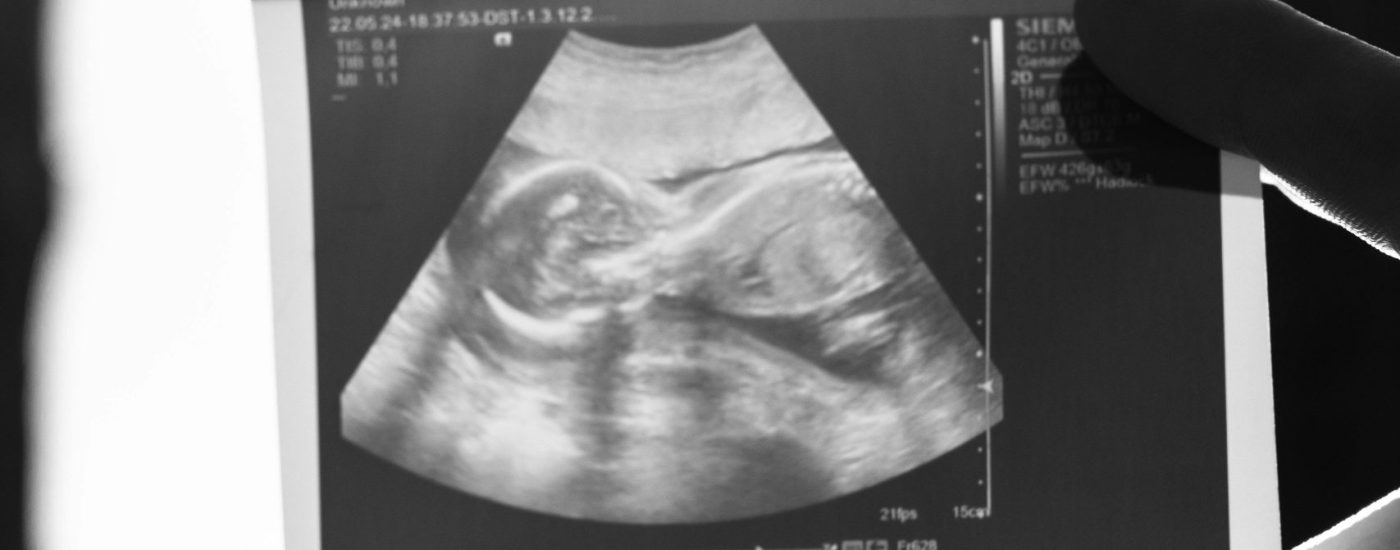

Descubre la magia de ver por primera vez a tu bebé en un entorno emotivo creado por nuestro equipo de Matronas. Equipados con la última tecnología en ecografía 5D y 6D, capturamos imágenes tridimensionales en movimiento y tiempo real.

Durante la sesión, los padres y familiares disfrutan de la imagen en vivo en una gran pantalla, mostrando detalles como el sexo, movimientos y la cara perfectamente formada del bebé. Esta experiencia, guiada por nuestras matronas especializadas, es emocional, no diagnóstica, brindando momentos inolvidables y la oportunidad de resolver todas tus dudas.

A partir de la semana 13, disfruta de una experiencia única donde podrás descubrir el sexo de tu bebé. Además, la ecografía incluye biometría fetal, peso estimado y el latido fetal.

Vive una experiencia única con nuestra Ecografía 5D, observa los gestos y movimientos de tu bebé, con detalles de biometría fetal, peso estimado, posición y latido fetal.